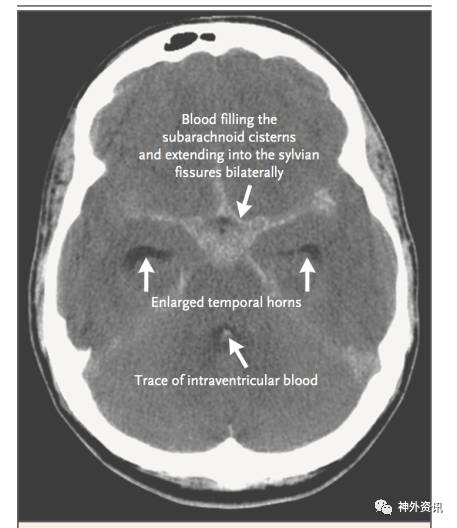

动脉瘤破裂后的初期治疗是指诊断明确之前需紧急防止危及生命的并发症,包括建立安全气道,稳定心血管功能和控制癫痫发作等。SAH分级系统最常用的两种是Hunt-Hess分级和WFNS分级,两种分级系统都重点评估脑损伤的严重程度。头颅CT平扫是诊断SAH首要检查手段(图2);起病后的前三天,CT扫描的灵敏度接近100%,但在5-7天后,其灵敏度下降到50%。头颅CT扫描还能显示血肿占位和急性脑积水。如果临床高度怀疑SAH,但CT扫描阴性,有必要作腰穿化验脑脊液。CTA可以检测到2mm大小的动脉瘤,但可能漏诊血泡状动脉瘤或因血栓形成的动脉瘤。DSA是诊断动脉瘤和指导治疗的金标准;三维血管重建结合二维血管重建有利于评估动脉瘤和选择治疗方案(图3)。药物干预可以降低动脉瘤再出血的风险;动脉瘤再破裂可进一步增加死亡率和加重神经功能障碍。SAH最初的24小时,动脉瘤再破裂风险为4%-14%。高血压提升动脉瘤再破裂的危险,但目标血压范围需进一步论证。抗纤维蛋白溶纤治疗可以稳定出血部位血栓,抗纤溶治疗的患者动脉瘤再破裂率为2%,而未抗纤溶治疗患者动脉瘤再破裂率为11%。但抗纤溶治疗并不能提高患者总体预后,而且可能增加深静脉血栓形成和迟发性脑缺血的发病率。20%的SAH患者出现癫痫发作,从而引起血流动力学不稳增加动脉瘤破裂再出血率;然而当前并没有RCT证据支持抗癫痫治疗和推荐常规药物预防癫痫。对于破裂动脉瘤实施开颅手术夹闭或介入栓塞的治疗是安全有效的;应推荐患者到手术量大的脑血管病中心和请经验丰富的专业医生救治。ISAT和BRAT两项RCT研究比较介入栓塞治疗和开颅手术夹闭的预后发现,手术夹闭动脉瘤的闭塞率高和复发率低,但术后1年随访发现,介入栓塞治疗的患者功能恢复更良好。对于颅内压增高或血肿压迫引起的局灶性神经功能缺损以及动脉瘤介入治疗困难时,需要作血管搭桥重建结合开颅夹闭动脉瘤治疗;对年龄小于40岁、神经功能良好的前循环动脉瘤患者,优先考虑开颅夹闭治疗。

图2. 头颅CT扫描示蛛网膜下腔出血。